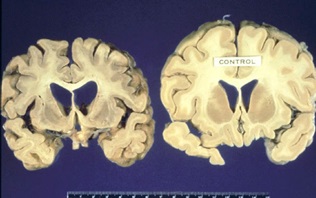

Τα νέα κρούσματα της νόσου στην Φθιώτιδα φέρνουν στην επικαιρότητα τα νοσήματα που προκαλούνται από την βρώση μολυσμένων κρεάτων και τη μετάδοση του παθολογικού μολυσματικού παράγοντα που προκαλεί τη νόσο, το πρίον. Το παθολογικό πρίον είναι ένα είδος πρωτεΐνης που προκαλεί αλλοιώσεις σε φυσιολογικές πρωτεΐνες του εγκεφάλου. Ζωονόσοι που οφείλονται σε παθολογικά πρίον είναι κυρίως η νόσος των τρελών αγελάδων στα βοοειδή και η τρομώδης νόσος των προβάτων. Τα νοσήματα prion στον άνθρωπο εκδηλώνονται κυρίως ως ασθένεια Creutzfeldt-Jakob με τις παραλλαγές της, σύνδρομο Gerstmann-Sträussler-Scheinker και kuru. Οι ασθένειες αυτές έχουν αλληλεπικαλυπτόμενα σημεία και συμπτώματα. Τα συμπτώματα περιλαμβάνουν ταχέως αναπτυσσόμενη άνοια, δυσκολία στο περπάτημα και τις αλλαγές στο βάδισμα, ψευδαισθήσεις, μυϊκή δυσκαμψία, σύγχυση, κούραση, δυσκολία στην ομιλία. Οι ασθένειες αυτές ονομάζονται και σπογγώδεις εγκεφαλοπάθειες λόγω του τύπου των αλλοιώσεων που προκαλούν στον εγκέφαλο όταν εξετάζεται στο μικροσκόπιο: Εμφανίζονται περιοχές βλάβης που μοιάζουν με σφουγγάρι. Φυσιολογικός εγκεφαλικός ιστός δεξιά και σε σπογγώδη…